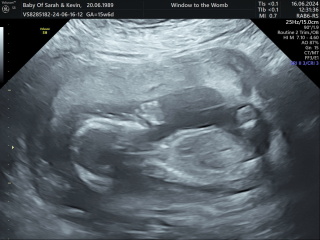

Lunamoon23 · 15/06/2024 12:24

@HopefulElle @RedRobyn2021 @littlepanda88 we did a test of the nub theory tech last night, and it came back with 90% probability of boy!! So it looks like everyone may well be correct!!

I've attached my nub theory results for fun!

Due December 2024